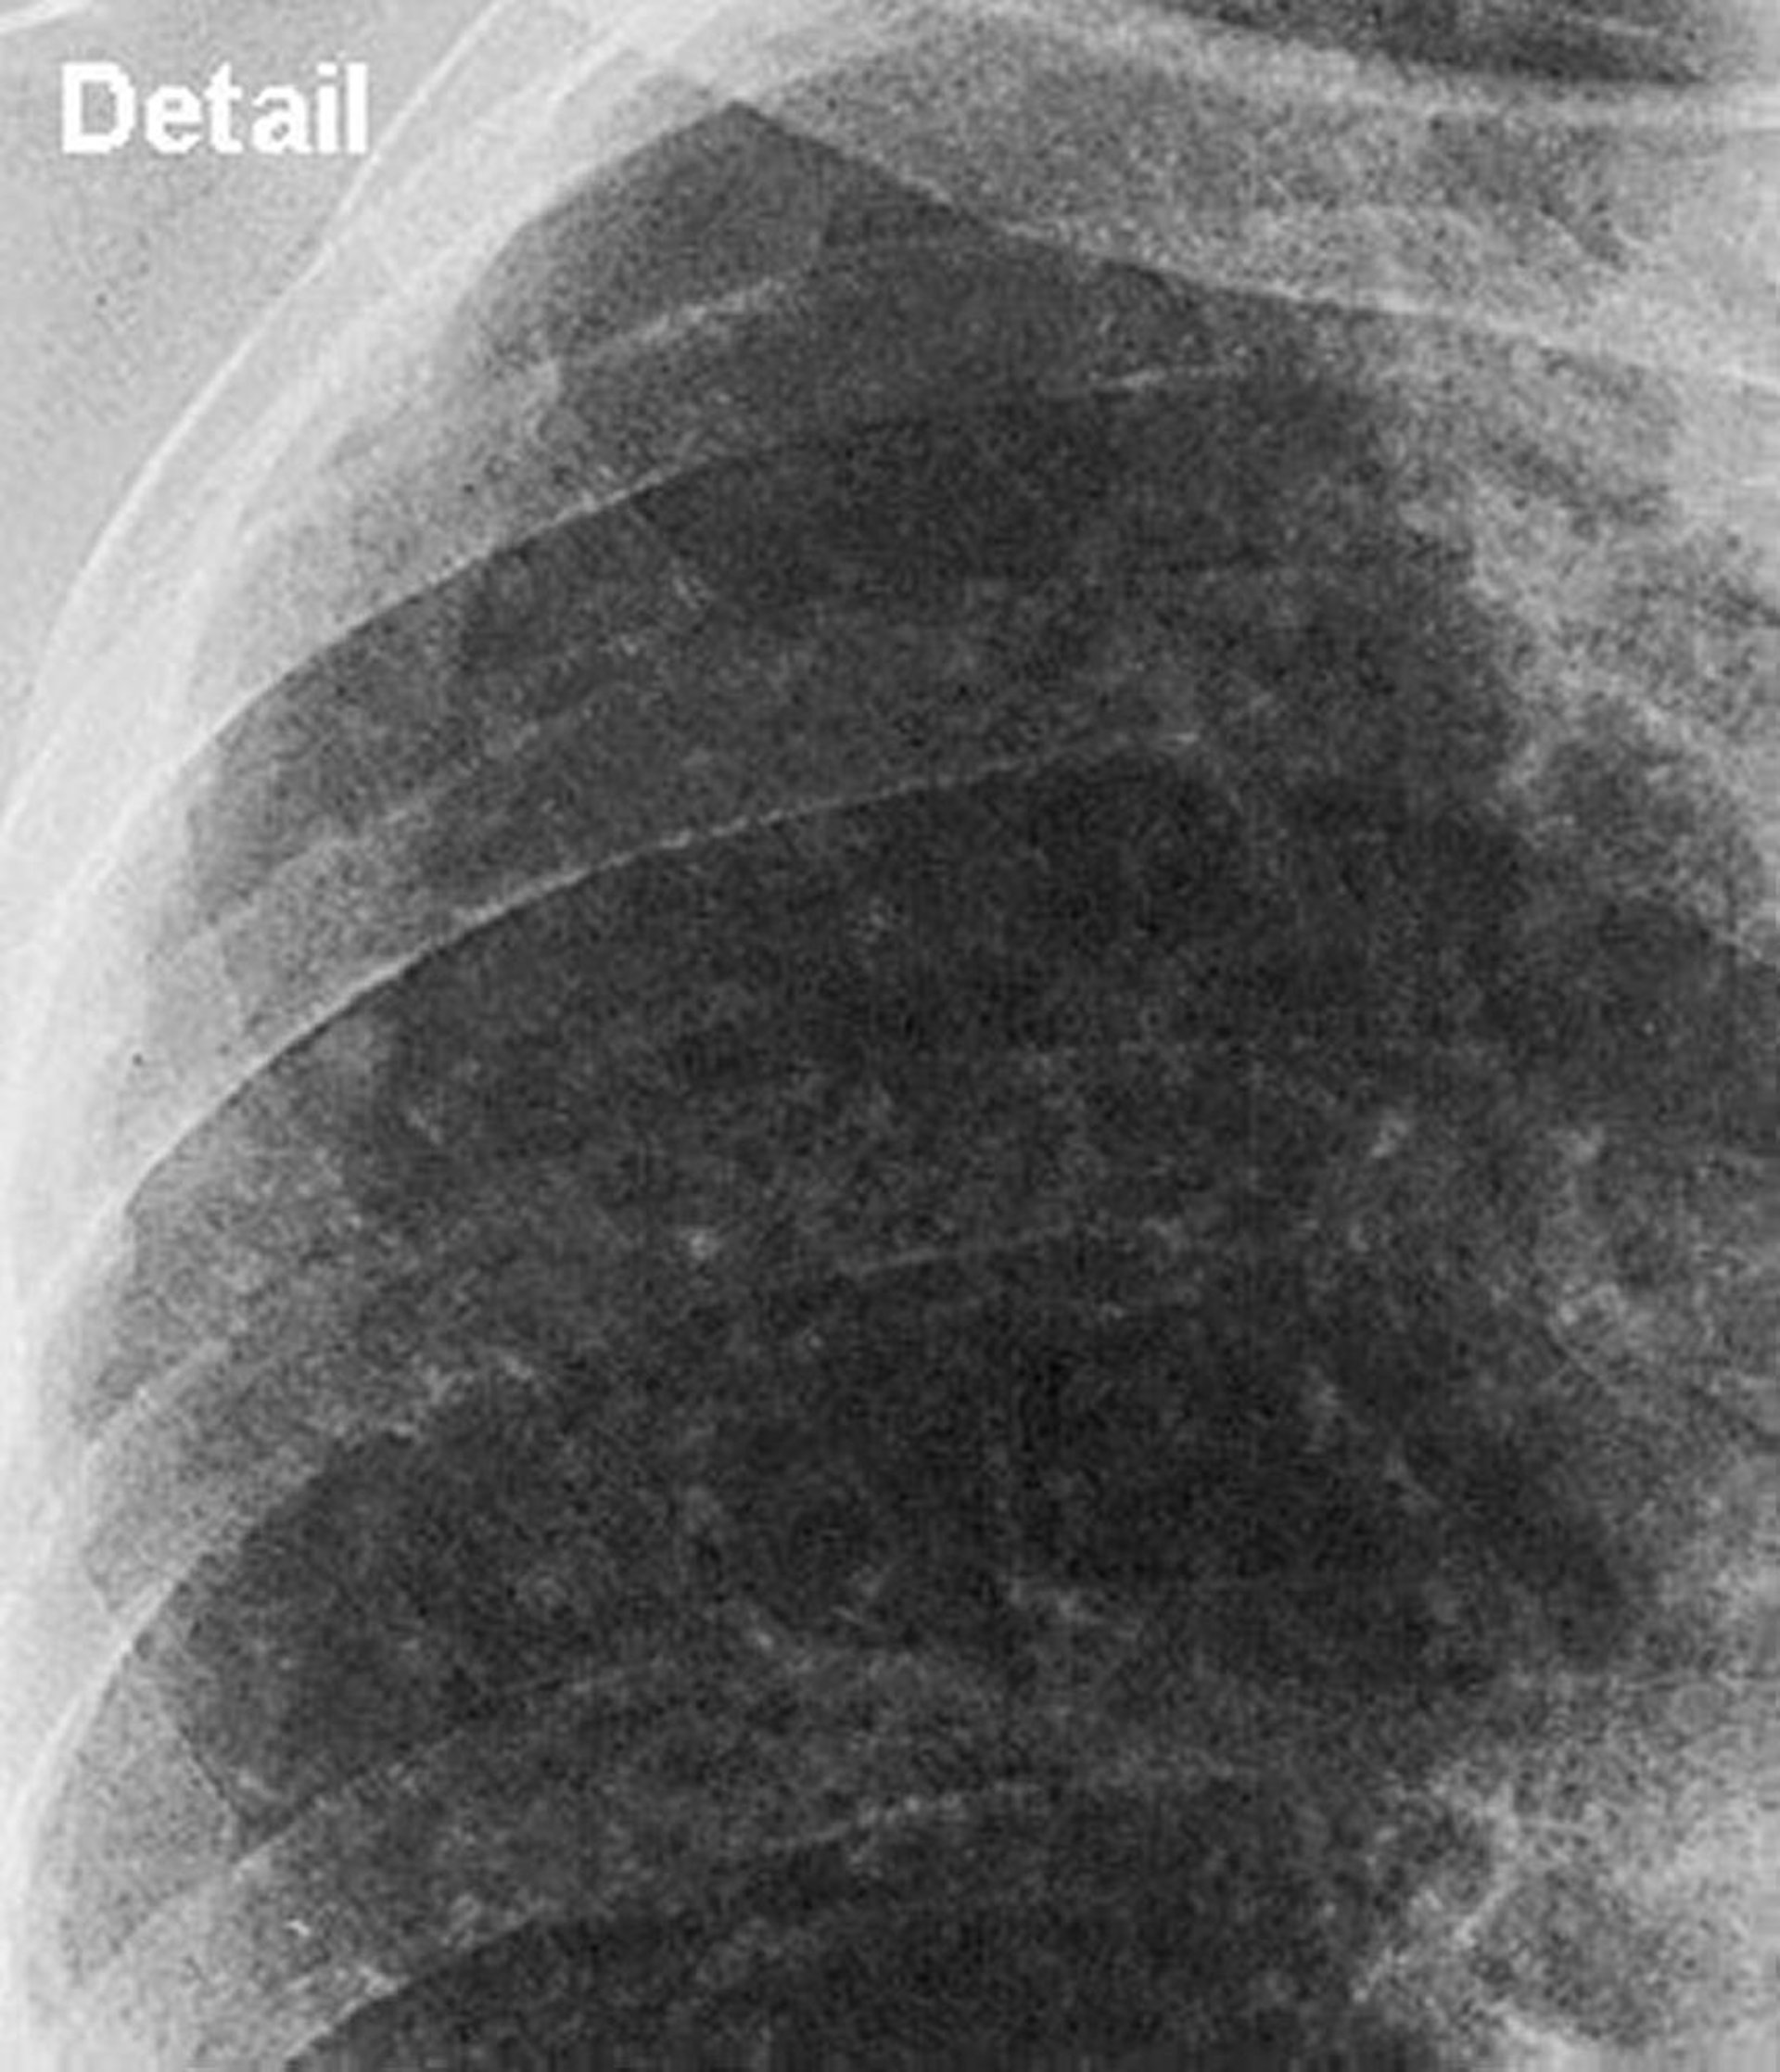

Close up view of upper lung field in simple silicosis.

Image courtesy of David W. Cugell, MD.